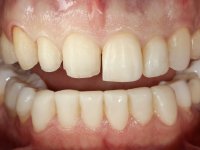

Paciente do sexo masculino, com 36 anos, não fumador. Fez tratamento ortodôntico e reabilitou esteticamente o sector anterior com restaurações em resina composta. As restaurações apresentavam um aumento vertical médio de 2 mm em relação o bordo incisal. Apresentavam-se esteticamente satisfatórias, mas com algumas fraturas incisais. O dente 1.5 apresentava um processo apical e o dente 2.6 apresentava tratamento endodôntico e uma lesão endo-periodontal. No maxilar inferior no local do dente 3.5 apresentava um implante com uma coroa aparafusada e o dente 8.5 ainda estava presente em boca com agenesia do dente 4.5. O paciente apresentava uma ligeira perda da dimensão vertical da oclusão provavelmente associada a um visível desgaste das superfícies oclusais. O periodonto era espesso e apresentava uma excelente higiene oral.

Após análise clínica e imagiológica foi proposto ao paciente recuperar a dimensão vertical da oclusão essencialmente à custa de incrementos oclusais inferiores utilizando “overlays” no sector posterior e facetas no sector anterior. A coroa aparafusada sobre o implante 3.5 seria substituída, no sentido de acompanhar este incremento. Na maxila o dente 2.6 teria extração indicada e posteriormente seria reabilitado com um implante e respetiva coroa. No sentido de reabilitar esteticamente o paciente duma forma minimamente invasiva, foi proposta a colocação de facetas feldespáticas no sector antero-superior. O objetivo de aumentar ligeiramente a D.V.O., teria como função “proteger” eficazmente o sector antero-superior.

Realizado o diagnóstico e tomada a decisão quanto ao tratamento a executar, tornou-se importante definir qual a sequência de trabalho a adotar no sentido de conseguir a reabilitação da D.V.O. (V.D.O), de forma progressiva e equilibrada. Na primeira fase fez-se uma pré-impressão da arcada inferior com silicone tipo “putty” e em seguida realizou-se o preparo dentário de todo o sector posterior. O preparo para os overlays foi feito coronalmente à linha amelo cementaria no sentido de ser o mais conservador possível. A impressão foi feita com técnica de dupla mistura após afastamento gengival realizado com pasta de caulino. A provisória foi realizada com resina composta de polimerização dual. Em laboratório foram realizados os overlays após se ter aberto ligeiramente (1,5mm) a D.V.O. nos modelos montados em articulador semi-ajustável. Simultaneamente o sector antero-inferior foi encerado no sentido de acompanhar este aumento da D.V.O. Também foi confecionada uma chave de silicone translucido para posterior confeção dos provisórios antero-inferiores. Em boca foi primeiro realizada a provisionalização dos dentes anteriores utilizando resina composta previamente aquecida após preparação das superfícies dentárias para a adesão. Foi colocado o dique de borracha para promover o isolamento absoluto e posteriormente foram colados os overlays. Em laboratório foi realizada nova chave de silicone para confecionar os provisórios antero-superiores. Seguidamente em boca foram preparados os seis dentes antero-superiores após colocação do fio de afastamento gengival. Feita a preparação adequada das superfícies dentárias foi realizada a impressão com técnica de dupla mistura e a respetiva provisória. Em laboratório foram confecionadas 6 facetas feldespáticas num modelo de trabalho tipo “Geller”. A provisória foi removida e as facetas foram coladas em boca utilizando um isolamento relativo competente. Esta opção foi tomada em virtude de uma prévia experiencia negativa com a colocação do dique de borracha na mandibula. Após a colagem dos laminados antero-superiores foram dadas 12 semanas para avaliar a adaptação do paciente à nova situação e então iniciar a confeção das facetas antero-inferiores. Após colocação do fio de afastamento gengival. foram feitos os preparos dentários adequados e em seguida foi feita a impressão. Também foi feita a preparação do dente 3.4 que, entretanto, tinha sofrido uma fratura do overlay. As facetas e a restauração do 3.4 foram realizadas num modelo de trabalho tipo “Geller”. Após remoção da provisória, as facetas foram coladas em boca, utilizando um isolamento relativo pelas razões apontadas anteriormente. Após colocação do trabalho o paciente foi reabilitado por outros colegas com um implante na zona do 2.6 e substituição da coroa aparafusada sobre o implante colocado no local do 3.5. Posteriormente surgiram fraturas nos overlays dos dentes 4.7 e 3.7 que foram reabilitados com overlays em Zr.